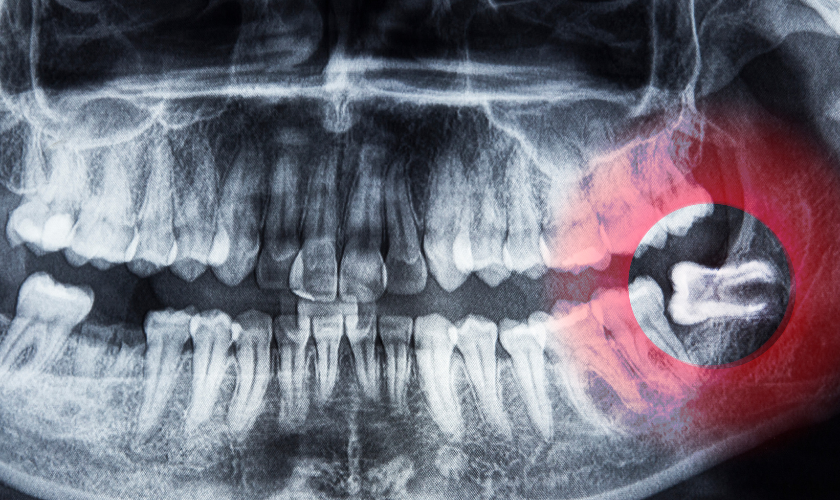

Wisdom teeth, also known as third molars, typically emerge between the ages of 17 and 25. When these teeth don’t have enough space to fully erupt or align properly, they can cause pain, swelling, and other discomforts.